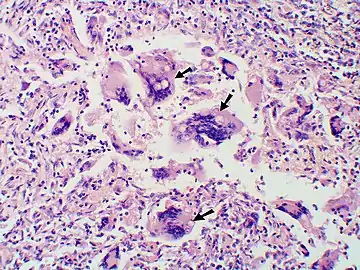

Granuloma with early suppuration. Fungal organisms difficult to recognize at this low magnification. Large yeast-like fungi seen within giant cells at arrows.

Large yeast-like fungi seen within giant cells at arrows. Large yeast-like fungi seen within giant cells at arrows. Budding yeasts in cytoplasm of giant cells at arrows. Broad-based budding and double contoured cell wall seen in the giant cell in the center is characteristic of Blastomyces dermatitidis.